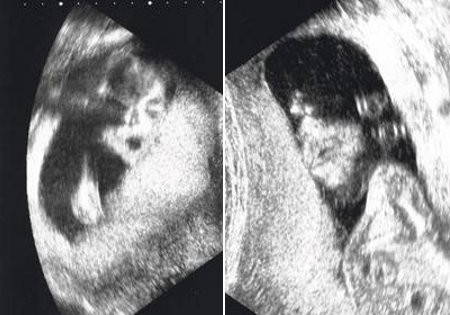

| Thai nhi giống ông vua nhạc Pop Michael Jackson. Năm 2009, đôi vợ chồng Dawn Kelley và William Hickman đã vô cùng ngỡ ngàng khi bức hình siêu âm đứa con gái 24 tuần tuổi của họ trông khá giống ông hoàng nhạc Pop Michael Jackson. Tuy nhiên, em bé sinh ra không giống như hình siêu âm. |